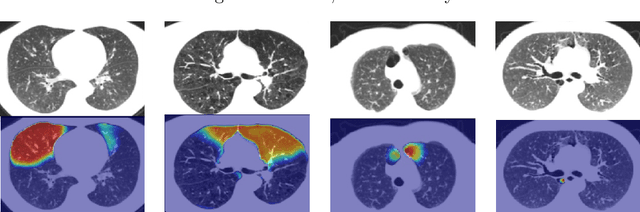

Abstract:Automatic lesion segmentation on thoracic CT enables rapid quantitative analysis of lung involvement in COVID- 19 infections. Obtaining voxel-level annotations for training segmentation networks is prohibitively expensive. Therefore we propose a weakly-supervised segmentation method based on dense regression activation maps (dRAM). Most advanced weakly supervised segmentation approaches exploit class activation maps (CAMs) to localize objects generated from high-level semantic features at a coarse resolution. As a result, CAMs provide coarse outlines that do not align precisely with the object segmentations. Instead, we exploit dense features from a segmentation network to compute dense regression activation maps (dRAMs) for preserving local details. During training, dRAMs are pooled lobe-wise to regress the per-lobe lesion percentage. In such a way, the network achieves additional information regarding the lesion quantification in comparison with the classification approach. Furthermore, we refine dRAMs based on an attention module and dense conditional random field trained together with the main regression task. The refined dRAMs are served as the pseudo labels for training a final segmentation network. When evaluated on 69 CT scans, our method substantially improves the intersection over union from 0.335 in the CAM-based weakly supervised segmentation method to 0.495.